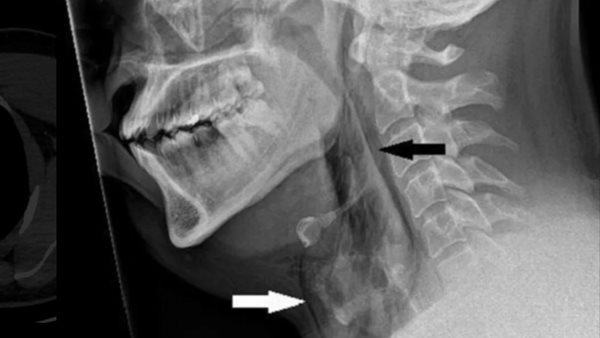

وكشفت الأشعة السينية أنه مصاب بانتفاخ الرئة الجراحي، عندما يعلق الهواء في أعمق الأنسجة تحت الجلد، وأظهرت الأشعة المقطعية أن التمزق كان بين العظمتين الثالثة والرابعة من رقبته وأن الهواء كان يتراكم في الفراغ بين الرئتين في صدره.